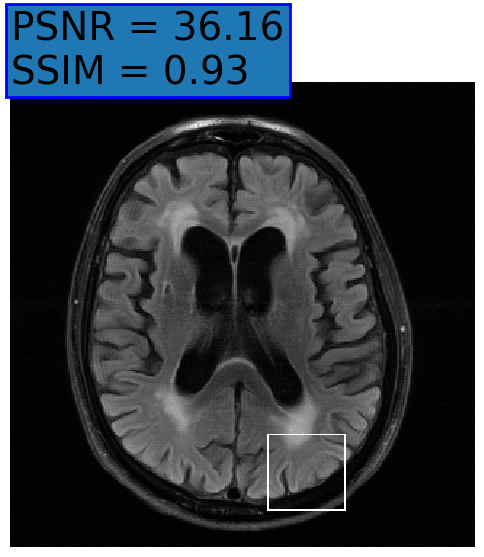

Figure 3: Examples of Reconstruction Results. Rows 1 and 3: The Ground truth (GT) fully sampled image, the reconstructed images obtained by the three models (1-3), NPB-REC, baseline, E2E-VarNet trained with Dropout, and the Std. map derived from our method for acceleration rates R=4𝑅4R=4, R=8𝑅8R=8, respectively. Rows 2 and 4: The corresponding annotated ROIS of the edema and resection cavity.

Fig. 3 presents examples of reconstruction results obtained by (1) our NPB-REC approach, (2) the baseline, and (3) Monte Carlo Dropout, for equispaced masks with two different acceleration rates R=4𝑅4R=4 and R=8𝑅8R=8. Table 1 presents the mean PSNR and SSIM metrics, calculated over the whole inference set, for the three models. our NPB-REC approach achieved significant improvements over the other methods in terms of PSNR and SSIM (Wilcoxon signed-rank test, pmuch-less-than\ll1e-4). The improvement in the reconstruction performance can be noted both quantitatively from the metrics especially for masks with acceleration rate R=8𝑅8R=8 and qualitatively via the images of annotations, where our results shows less smoothness than that obtained by Dropout.